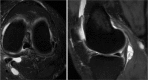

Context: Popliteal synovial cysts, also known as Baker's cysts, are commonly found in association with intra-articular knee disorders, such as osteoarthritis and meniscus tears. Histologically, the cyst walls resemble synovial tissue with fibrosis evident, and there may be chronic nonspecific inflammation present. Osteocartilaginous loose bodies may also be found within the cyst, even if they are not seen in the knee joint. Baker's cysts can be a source of posterior knee pain that persists despite surgical treatment of the intra-articular lesion, and they are routinely discovered on magnetic resonance imaging scans of the symptomatic knee. Symptoms related to a popliteal cyst origin are infrequent and may be related to size.

Conclusion: A capsular opening to the semimembranosus-medial head gastrocnemius bursa is a commonly found normal anatomic variant. It is thought that this can lead to the formation of a popliteal cyst in the presence of chronic knee effusions as a result of intra-articular pathology. Management of symptomatic popliteal cysts is conservative. The intra-articular pathology should be first addressed by arthroscopy. If surgical excision later becomes necessary, a limited posteromedial approach is often employed. Other treatments, such as arthroscopic debridement and closure of the valvular mechanism, are not well studied and cannot yet be recommended.